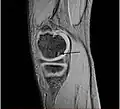

Magnetic resonance imaging (MRI) is useful for staging OCD lesions, evaluating the integrity of the joint surface, and distinguishing normal variants of bone formation from OCD by showing bone and cartilage edema in the area of the irregularity. MRI provides information regarding features of the articular cartilage and bone under the cartilage, including edema, fractures, fluid interfaces, articular surface integrity, and fragment displacement.[37][38] A low T1 and high T2 signal at the fragment interface is seen in active lesions. This indicates an unstable lesion or recent microfractures.[30] While MRI and arthroscopy have a close correlation, X-ray films tend to be less inductive of similar MRI results.[38]

Sagittal MRI: Linear low T1 signal at the articular surfaces of the lateral aspects of the medial condyle of the femur confirms the presence of OCD. -